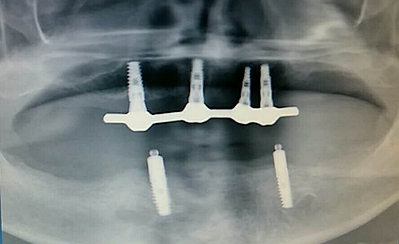

毛國斌種植病例——群討論分享